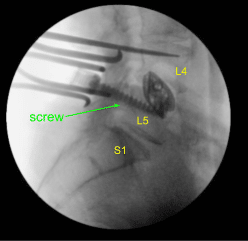

Given the concern for the implant in the prone position and our feeling that the endplates may have fractured more, we exposed the transverse processes for L4 and L5 and used the drill to create pilot holes in the pedicle on the left side at L4 and L5. Under fluoroscopy, we guided probes through the pedicles and tapped each pedicle, then placed pedicle screws into L4 and L5.

These screws were stimulated, and checked under fluoroscopy, and then a rode was placed and cap screws were given a final tightened. On the right side and left side, we decorticated the facets and transverse processes and placed our fusion mass for arthrodesis.